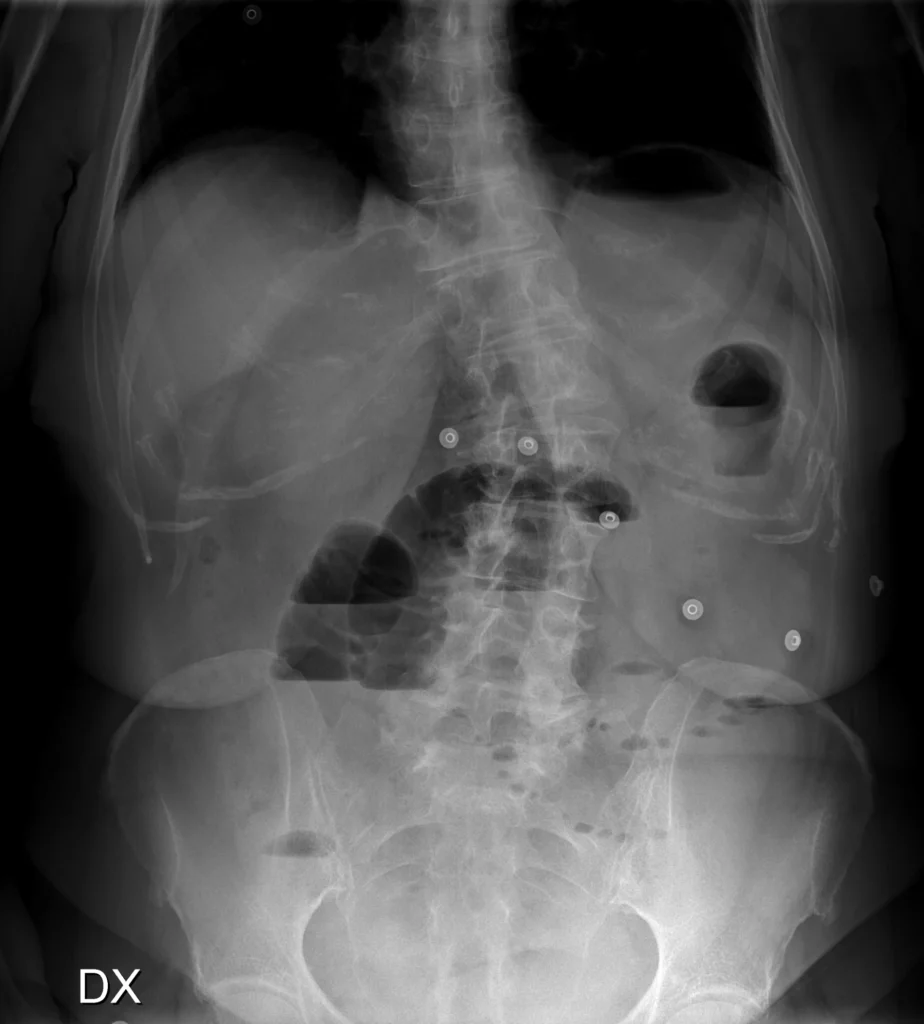

Rx de abdomen AP con paciente en bipedestación. Asas intestinales dilatadas y con niveles hidroaéreos. La posición central en el abdomen y la imagen de las válvulas conniventes indica qué se trata de intestino delgado (yeyuno). En el cuadrante inferior izquierdo del abdomen se observan múltiples pequeñas burbujas de gas adyacentes, dispuestas longitudinalmente, que configuran el “collar de perlas”.

El signo del collar de perlas (también descrito como string of pearls o string of beads) consiste en una hilera de pequeñas burbujas de aire orientadas longitudinalmente. Corresponden a pequeñas cantidades de gas atrapadas entre las válvulas conniventes a lo largo de la pared no dependiente de asas de intestino delgado dilatadas y llenas de líquido. El contraste gas–líquido permite verlo en la Rx.

En el contexto clínico adecuado, este signo se considera virtualmente diagnóstico de obstrucción mecánica del intestino delgado.